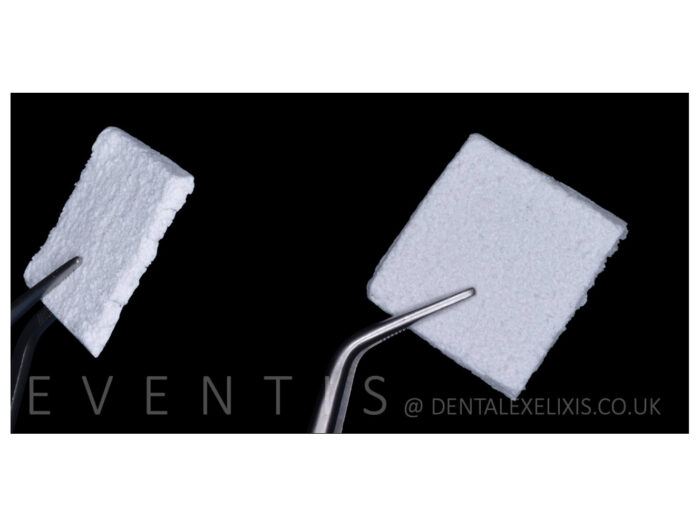

Flexible Graft składa się z β-TCP z dodatkiem krzemianu osadzonego wewnątrz syntetycznej sieci polimerowej na bazie PLA o różnej grubości. Unikalne mikro- i makroporowate struktury, które najbardziej przypominają architekturę naturalnych ludzkich kości. Stopniowo rozpuszcza się w organizmie, wspomagając tworzenie nowej kości

- Biomateriał składa się z ß-TCP z dodatkiem krzemionki 50/50%, osadzonym w syntetycznej siatce polimerowej na bazie PLA o różnych grubościach.